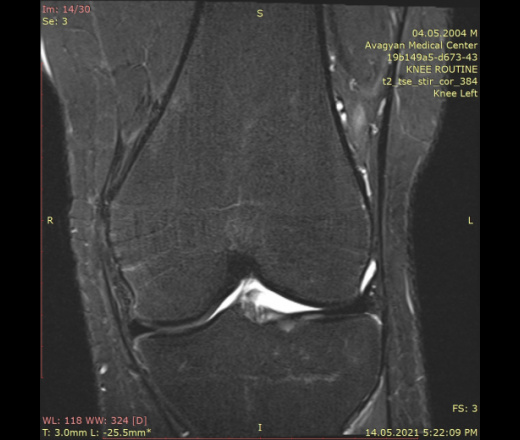

17лет, мужчина, рассеянная боль в левом коленном суставе, прыгнул в бассейн, думая, что глубокий, а оказался 50 см. Приземлился неожиданно и неудачно. 5-6 лет назад был ушиб того же колена, во время бега по коридору школы внезапно открыли дверь перед ним, и он сиьлно ударил коленум об дверы. Тогда сказали, что в суставе накоплен кровь (делали либо рентген, либо УЗИ), надели ортопедическй наколенник пару недель, и боль прошло.

МРТ левого коленного сустава

• t2_tse_stir_cor_384

МРТ левого коленного сустава ID:88035

Нет определенного дигноза. Уважаемые доктора, хочу получить ваши заключении по МРТ.

Перелом задне-латерального угла большеберцевой кости.